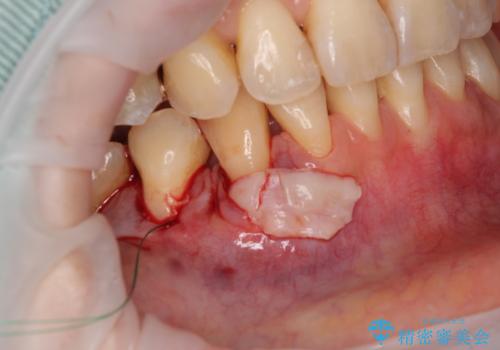

口蓋(上顎の内側)から採取した結合組織(歯肉の内側の組織)を移植することによる、根面被覆術を行うこととしました。

移植片には、極力角化歯肉が多く残るようにし、被覆するだけでなく、歯肉の厚みを増やし、角化歯肉を回復させることができました。